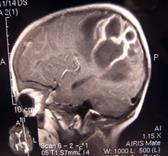

Рис. 39. МРТ исследование у пациентов с внутричерепными кистами

и аневризмой вены Галена.